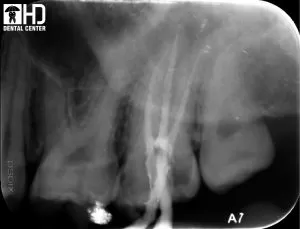

1/ Chữa tủy răng cối lớn hàm trên

Đây là trường hợp chữa tủy răng cối lớn hàm trên, chân răng dài, ống tủy hẹp và cong. Sử dụng trâm Wave-one, chúng tôi đã sửa soạn được hết chiều dài của ông tủy, lấy sạch tủy và tạo độ thuôn cho ống tủy, sau đó trám bít ống tủy bằng gutta percha. Các bạn có thể nhìn thấy trên film X quang sau khi chữa tủy, những đường màu trắng ở trong răng là hình ảnh của gutta percha được dùng để trám bít ống tủy